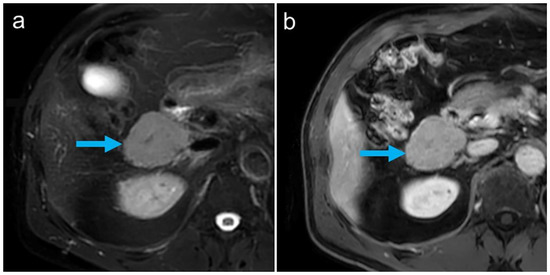

All abdominal and pelvic masses showed a high tracer uptake increasing over time (Figure 2), with the highest uptake values measured in the subhepatic index lesion (Figure 1 and Figure 2, arrows): SUVmean: 69.1/94.1 at 10/25 min after tracer injection, respectively, showing an increase of 36% between the two time points. During the same interval, blood pool activity decreased (SUVmean: 9.6/6.8, −29%), indicating the removal of the labeled, heat-damaged RBCs from the blood by the functioning splenic tissue. The diagnosis of disseminated splenosis was confirmed. Since no symptoms were present and there was no evidence of an increased susceptibility to infections, no further treatment was necessary.

Figure 2. Multiple masses with high tracer uptake seen on RBC-PET/CT (a): non-contrast CT, (b): PET/CT fusion, (c): PET maximum intensity projection (MIP) image acquired 25 min after tracer injection).